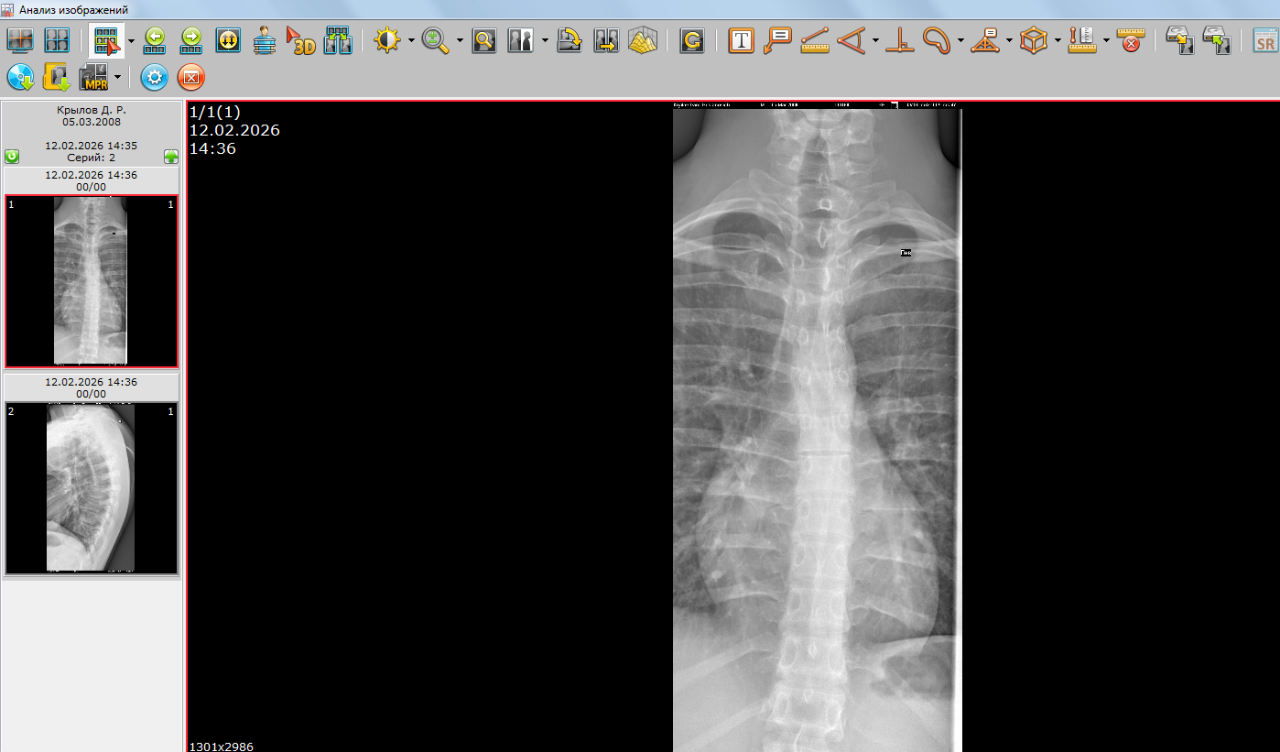

Открыты ли зоны роста на данных снимках

Хронические заболевания: Сколиоз, плоскостопие.

Здравствуйте, можно ли по данным снимкам определить открыты ли зоны роста? А также совпадает ли костный возраст с паспортным? Мой рост 174 см, Рост отца 176 см, рост мамы 158см. За год вырос на 3 см. Заранее спасибо.